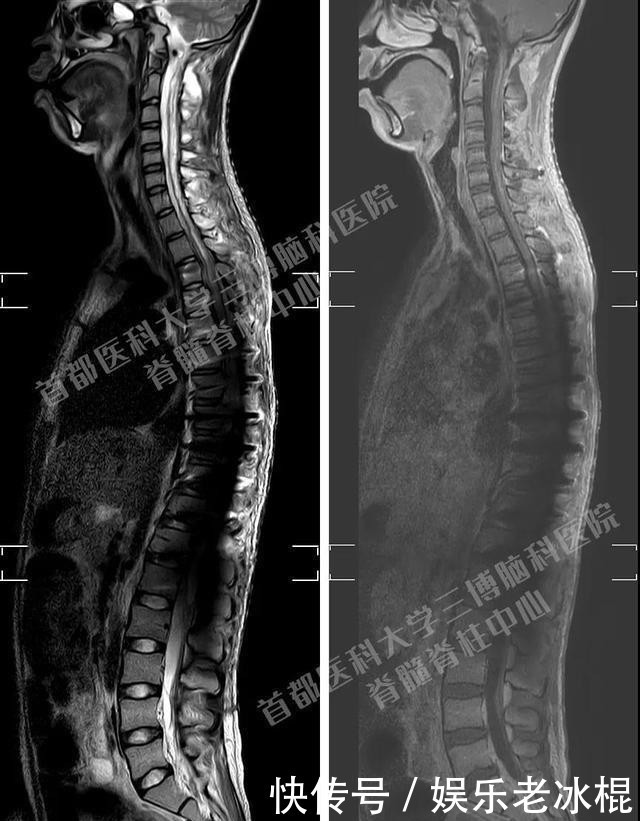

术后脊柱全长CT重建提示内固定位置良好

术后核磁示脊髓内肿瘤全切除,脊髓形态比较好,脊柱的生理曲度正常术后小王自主呼吸好,顺利脱机拔管,血压心率稳定。患者肌力已恢复至术前水平,可以自主吃饭,坐立,进一步康复提高指日可待。更幸运的是病理回报:毛细胞星形细胞瘤(WHOI级),肿瘤性质偏良性,不需进行放疗或化疗,预后良好。未来,对于小王来说,又充满了期待。也希望他早日康复,在花季样年华中继续绽放青春。(钱宇阳)【来源:首医大三博脑科医院】声明:转载此文是出于传递更多信息之目的。若有来源标注错误或侵犯了您的合法权益,请作者持权属证明与本网联系,我们将及时更正、删除,谢谢。 邮箱地址:newmedia@xxcb.cn谢谢您的观看